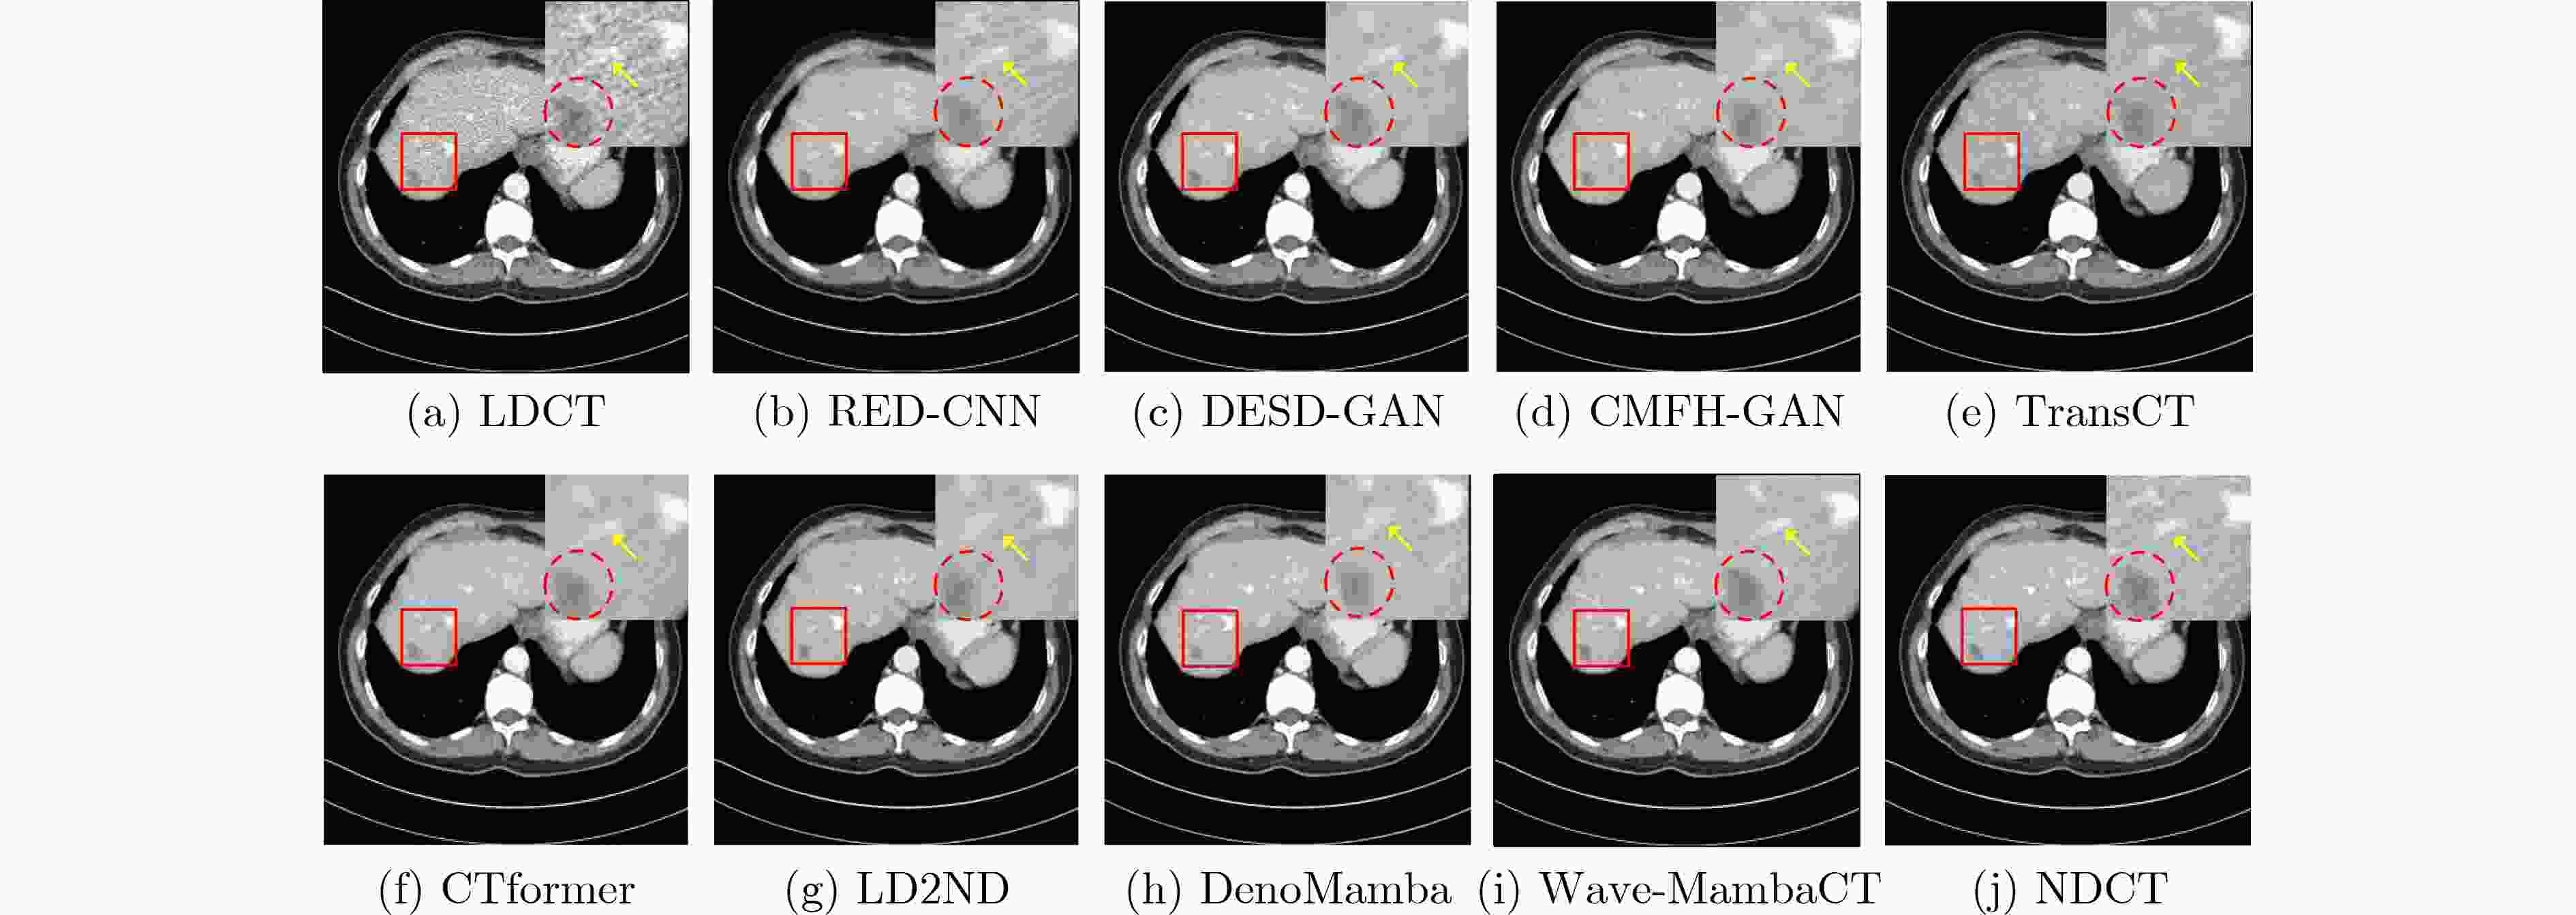

Objective Low-Dose Computed Tomography (LDCT) reduces patient radiation exposure but introduces substantial noise and artifacts into reconstructed images. Convolutional Neural Network (CNN)-based denoising approaches are limited by local receptive fields, which restrict their abilities to capture long-range dependencies. Transformer-based methods alleviate this limitation but incur quadratic computational complexity relative to image size. In contrast, State Space Model (SSM)–based Mamba frameworks achieve linear complexity for long-range interactions. However, existing Mamba-based methods often suffer from information loss and insufficient noise suppression. To address these limitations, we propose the Wave-MambaCT model. Methods The proposed Wave-MambaCT model adopts a multi-scale framework that integrates Discrete Wavelet Transform (DWT) with a Mamba module based on the SSM. First, DWT performs a two-level decomposition of the LDCT image, decoupling noise from Low-Frequency (LF) content. This design directs denoising primarily toward the High-Frequency (HF) components, facilitating noise suppression while preserving structural information. Second, a residual module combined with a Spatial-Channel Mamba (SCM) module extracts both local and global features from LF and HF bands at different scales. The noise-free LF features are then used to correct and enhance the corresponding HF features through an attention-based Cross-Frequency Mamba (CFM) module. Finally, inverse wavelet transform is applied in stages to progressively reconstruct the image. To further improve denoising performance and network stability, multiple loss functions are employed, including L1 loss, wavelet-domain LF loss, and adversarial loss for HF components. Results and Discussions Extensive experiments on the simulated Mayo Clinic datasets, the real Piglet datasets, and the hospital clinical dataset DeepLesion show that Wave-MambaCT provides superior denoising performance and generalization. On the Mayo dataset, a PSNR of 31.6528 is achieved, which is higher than that of the suboptimal method DenoMamba (PSNR31.4219 ), while MSE is reduced to0.00074 and SSIM and VIF are improved to0.8851 and0.4629 , respectively (Table 1 ). Visual results (Figs. 4 –6 ) demonstrate that edges and fine details such as abdominal textures and lesion contours are preserved, with minimal blurring or residual artifacts compared with competing methods. Computational efficiency analysis (Table 2 ) indicates that Wave-MambaCT maintains low FLOPs (17.2135 G) and parameters (5.3913 M). FLOPs are lower than those of all networks except RED-CNN, and the parameter count is higher only than those of RED-CNN and CTformer. During training, 4.12 minutes per epoch are required, longer only than RED-CNN. During testing,0.1463 seconds are required per image, which is at a medium level among the compared methods. Generalization tests on the Piglet datasets (Figs. 7 ,8 ,Tables 3 ,4 ) and DeepLesion (Fig. 9 ) further confirm the robustness and generalization capacity of Wave-MambaCT.In the proposed design, HF sub-bands are grouped, and noise-free LF information is used to correct and guide their recovery. This strategy is based on two considerations. First, it reduces network complexity and parameter count. Second, although the sub-bands correspond to HF information in different orientations, they are correlated and complementary as components of the same image. Joint processing enhances the representation of HF content, whereas processing them separately would require a multi-branch architecture, inevitably increasing complexity and parameters. Future work will explore approaches to reduce complexity and parameters when processing HF sub-bands individually, while strengthening their correlations to improve recovery. For structural simplicity, SCM is applied to both HF and LF feature extraction. However, redundancy exists when extracting LF features, and future studies will explore the use of different Mamba modules for HF and LF features to further optimize computational efficiency.Conclusions Wave-MambaCT integrates DWT for multi-scale decomposition, a residual module for local feature extraction, and an SCM module for efficient global dependency modeling to address the denoising challenges of LDCT images. By decoupling noise from LF content through DWT, the model enables targeted noise removal in the HF domain, facilitating effective noise suppression. The designed RSCM, composed of residual blocks and SCM modules, captures fine-grained textures and long-range interactions, enhancing the extraction of both local and global information. In parallel, the Cross-band Enhancement Module (CEM) employs noise-free LF features to refine HF components through attention-based CFM, ensuring structural consistency across scales. Ablation studies ( Table 5 ) confirm the essential contributions of both SCM and CEM modules to maintaining high performance. Importantly, the model’s staged denoising strategy achieves a favorable balance between noise reduction and structural preservation, yielding robustness to varying radiation doses and complex noise distributions.-